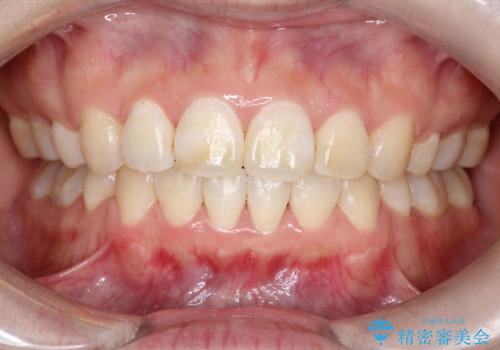

- ”口元を下げたい”が主訴で来院されました。

抜歯してワイヤー矯正を行い、口元も改善され大変満足していただきました。

小臼歯の抜歯を行うことで口元を改善することができました。